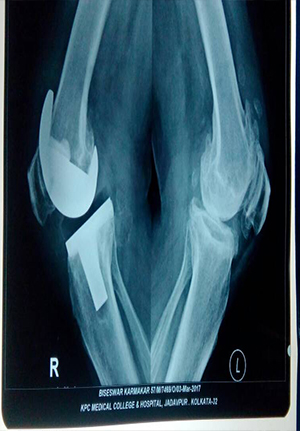

Total Knee Replacement

Reduction and internal fixation for proximal tibial fracture

before operation

After operation